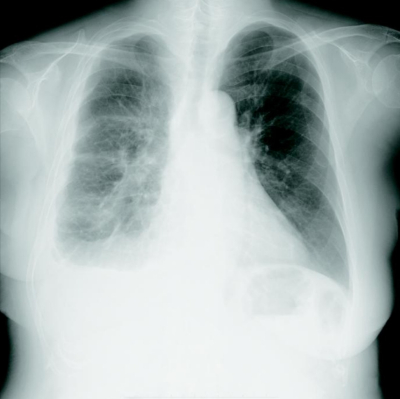

65 歳の女性。胸痛を主訴に来院した。1か月前から右胸痛を自覚していたが改善しないため受診した。13 年前に右乳癌で手術の既往がある。30 年前から建設業に従事していた。呼吸音は右下胸部で減弱、胸部の打診で右背側に濁音を認めた。

胸部エックス線写真、胸部造影CT及びFDG-PET/CTを別に示す。胸腔鏡下生検を施行した結果、カルレチニン免疫組織染色が陽性である悪性細胞を認めた。